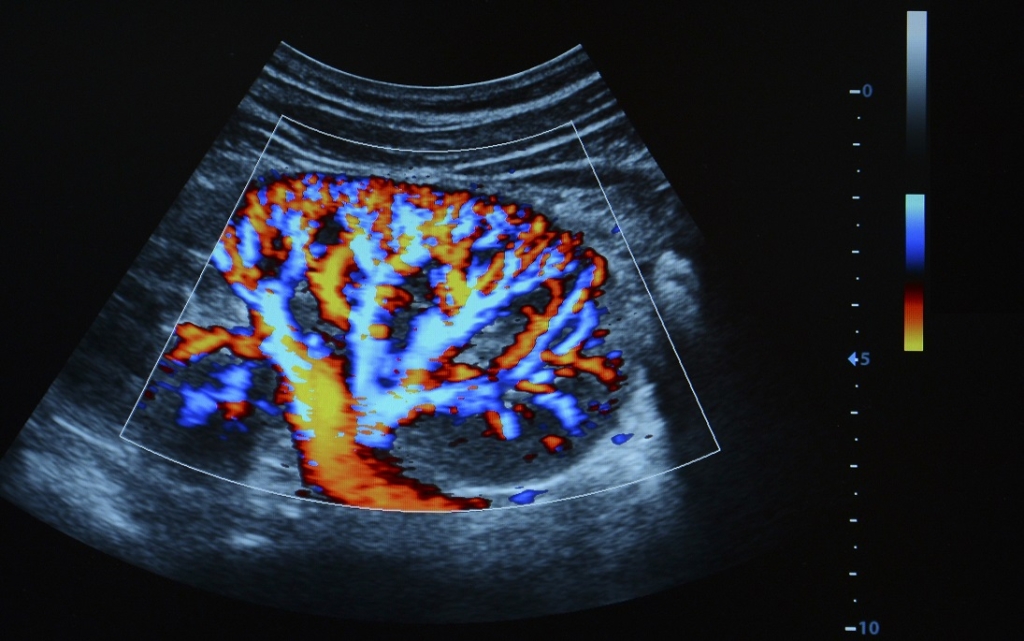

La scoperta di un tumore del rene avviene in prima battuta attraverso un’ecografia addominale, che nel sessanta per cento delle diagnosi nel 2016 era stata effettuata però per altre ragioni. Una fortuna, verrebbe da dire: merito del sempre maggiore ricorso alla diagnostica per immagini, che ha reso la diagnosi attraverso la palpazione di una massa a livello del fianco qualcosa di sempre più raro. Ma in realtà dietro questo dato, diffuso in occasione della giornata mondiale contro il tumore del rene, si celano due aspetti: la modalità subdola con cui spesso si manifesta la malattia (ma attenzione alla presenza di sangue nelle urine) e la scarsa attenzione riposta nei confronti dei fattori di rischio.

Le diagnosi casuali sono in realtà una manna dal cielo. Scoprire un tumore del rene quando i sintomi non sono ancora presenti equivale ad avere portato a termine una diagnosi precoce. Ovvero ad avere maggiori chance di salvare il paziente. In Italia la sopravvivenza a cinque anni dalla diagnosi raggiunge il 80 per cento e vivono più di 118.000 persone che hanno messo alle spalle un tumore del rene. L’intervento chirurgico, possibilmente conservativo (oggi attuato spesso con la chirurgia robotica), non di rado è sufficiente anche da solo per raggiungere l’obiettivo della guarigione. Ma dal momento che la malattia può essere diagnosticata in fase metastatica e che una diagnosi su quattro tende a recidivare, importante è anche l’intervento farmacologico. Nel cancro del rene la chemioterapia e la radioterapia si sono dimostrate, storicamente, poco efficaci. Quale soluzione adottare, allora? «Per le persone con neoplasia in fase metastatica, i farmaci a bersaglio molecolare hanno permesso di allungare la sopravvivenza di oltre due anni - aggiunge Camillo Porta, oncologo medico al policlinico San Matteo di Pavia -. Si tratta di farmaci antiangiogenici, che inibiscono la capacità di formare nuovi vasi sanguigni».